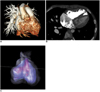

Fig. 9

Combo CT scan comprised of non-ECG-synchronized spiral scan with usual scan range (A, B) and prospective ECG-triggered sequential scan with narrow scan range confined to conotruncal area of heart (C, D) in 9-months-old boy with Williams syndrome. Supravalvular aortic stenosis (arrows on C) and combined valvar (arrow on D) and subvalvar (arrowheads on D) pulmonary stenoses are clearly shown on prospective ECG-triggered sequential CT images (C, D). Dose estimates are 1.6 mSv for non-ECG-synchronized spiral scan and 0.2 mSv for prospective ECG-triggered sequential scan.